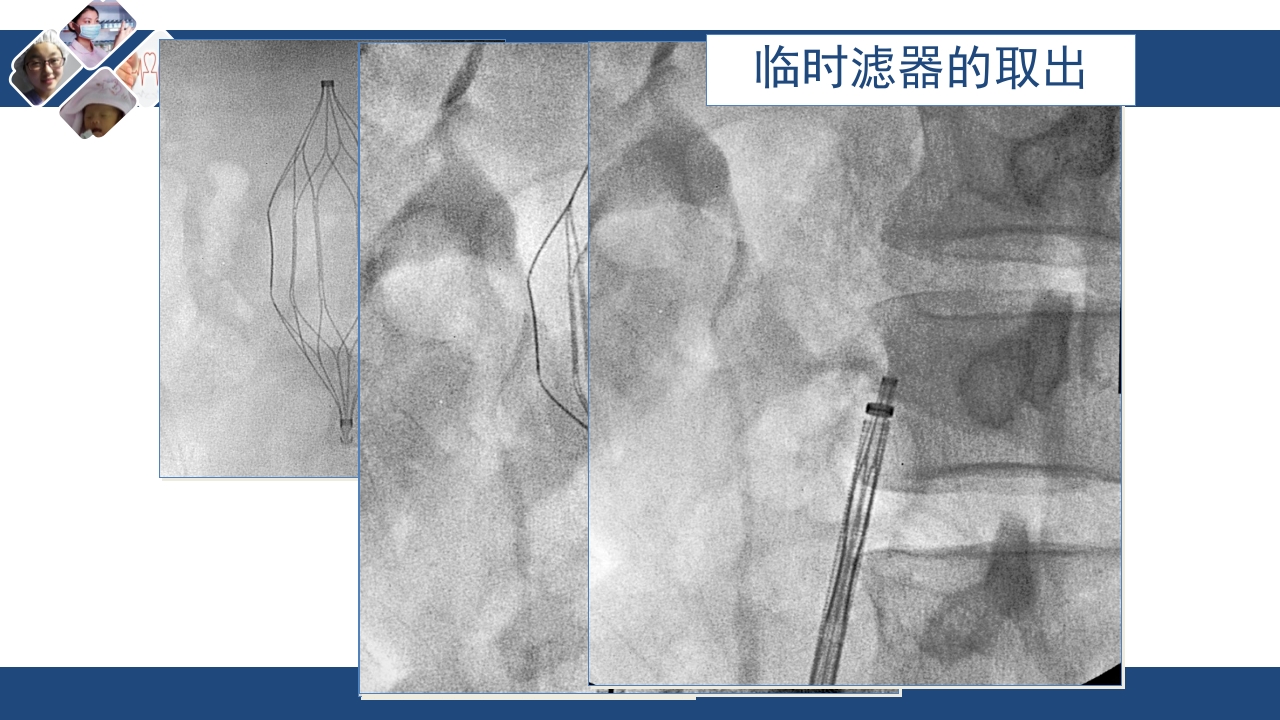

<p>单击此处编辑母版文本样式 第二级 第三级 第四级 第五级 血管外科:xxx 时间:xxx 2025-4-2 1 单击此处编辑母版标题样式 单击此处编辑母版文本样式 1 什么是VTE? 第二级 第三级 2 VTE的发病机制第四级 第五级 3 VTE的表现和诊断 4 VTE的治疗 5 VTE的预防 Zhanfeng Sun, Weiliang Jiang, et al. 2025-4-2 2 什么是VTE? Zhanfeng Sun, Weiliang Jiang, et al. 静脉血栓栓塞症(VTE)的概念 静脉血栓栓塞症(Venous thromboembolism)简称VTE,是 指血液在静脉内不正常的凝固, 使管腔部分或完全阻塞 VTE主要包括深静脉血栓形成 (Deep vein thrombosis,DVT)和 肺栓塞(Pulmonary Embolism , PE) VTE为常见病症,是患者发病和 死亡的重要原因之一1,2 Zhanfen...